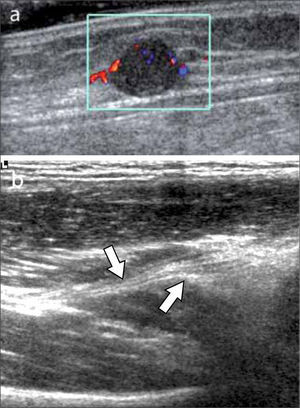

Ecografía muscularSu indicación más frecuente es para evaluación de desgarros, con distintas manifestaciones y clasificaciones dependiendo del mecanismo, del grado de lesión, la localización y la anatomía de los distintos músculos (1, 5, 6).

Los más frecuentes son los indirectos por distensión de músculos que atraviesan dos articulaciones.

Se puede encontrar desgarros desde bajo grado fibrilares, parciales fasciculares, hasta completos, con presencia variable de hematomas o colecciones líquidas de distinto tamaño. Según su localización en el músculo pueden ser intrasustancia, periféricos miofasciales o en la unión miotendínea (figura 12). En el caso de trauma directo puede haber rotura por compresión contra el hueso o laceración por herida penetrante.

Cabe mencionar que en ocasiones desgarros pequeños pueden no ser evidentes a la ecografía en las primeras 24-48 horas, por lo cual si la clínica es concordante y el US negativo, se sugiere una re-evaluación ecográfica posterior.

Según la evolución, en el tiempo se pueden encontrar cicatrices fibrosas, zonas de re-desgarro o hernias musculares por rotura de la fascia.